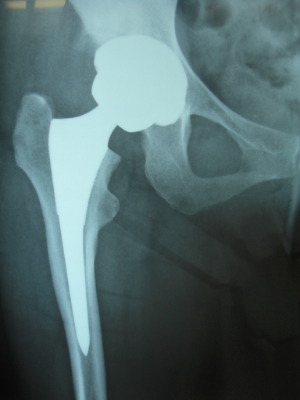

58歳 大腿骨頭壊死 MIS-DAによる右人工股関節置換術

術後2日で離床、3日めに歩行器歩行訓練開始、5日で杖歩行、7日で杖なし歩行可能となり2週で退院

大腿骨頭壊死症のレントゲン像(A)と骨頭断面(B)およびTHA術後(C)